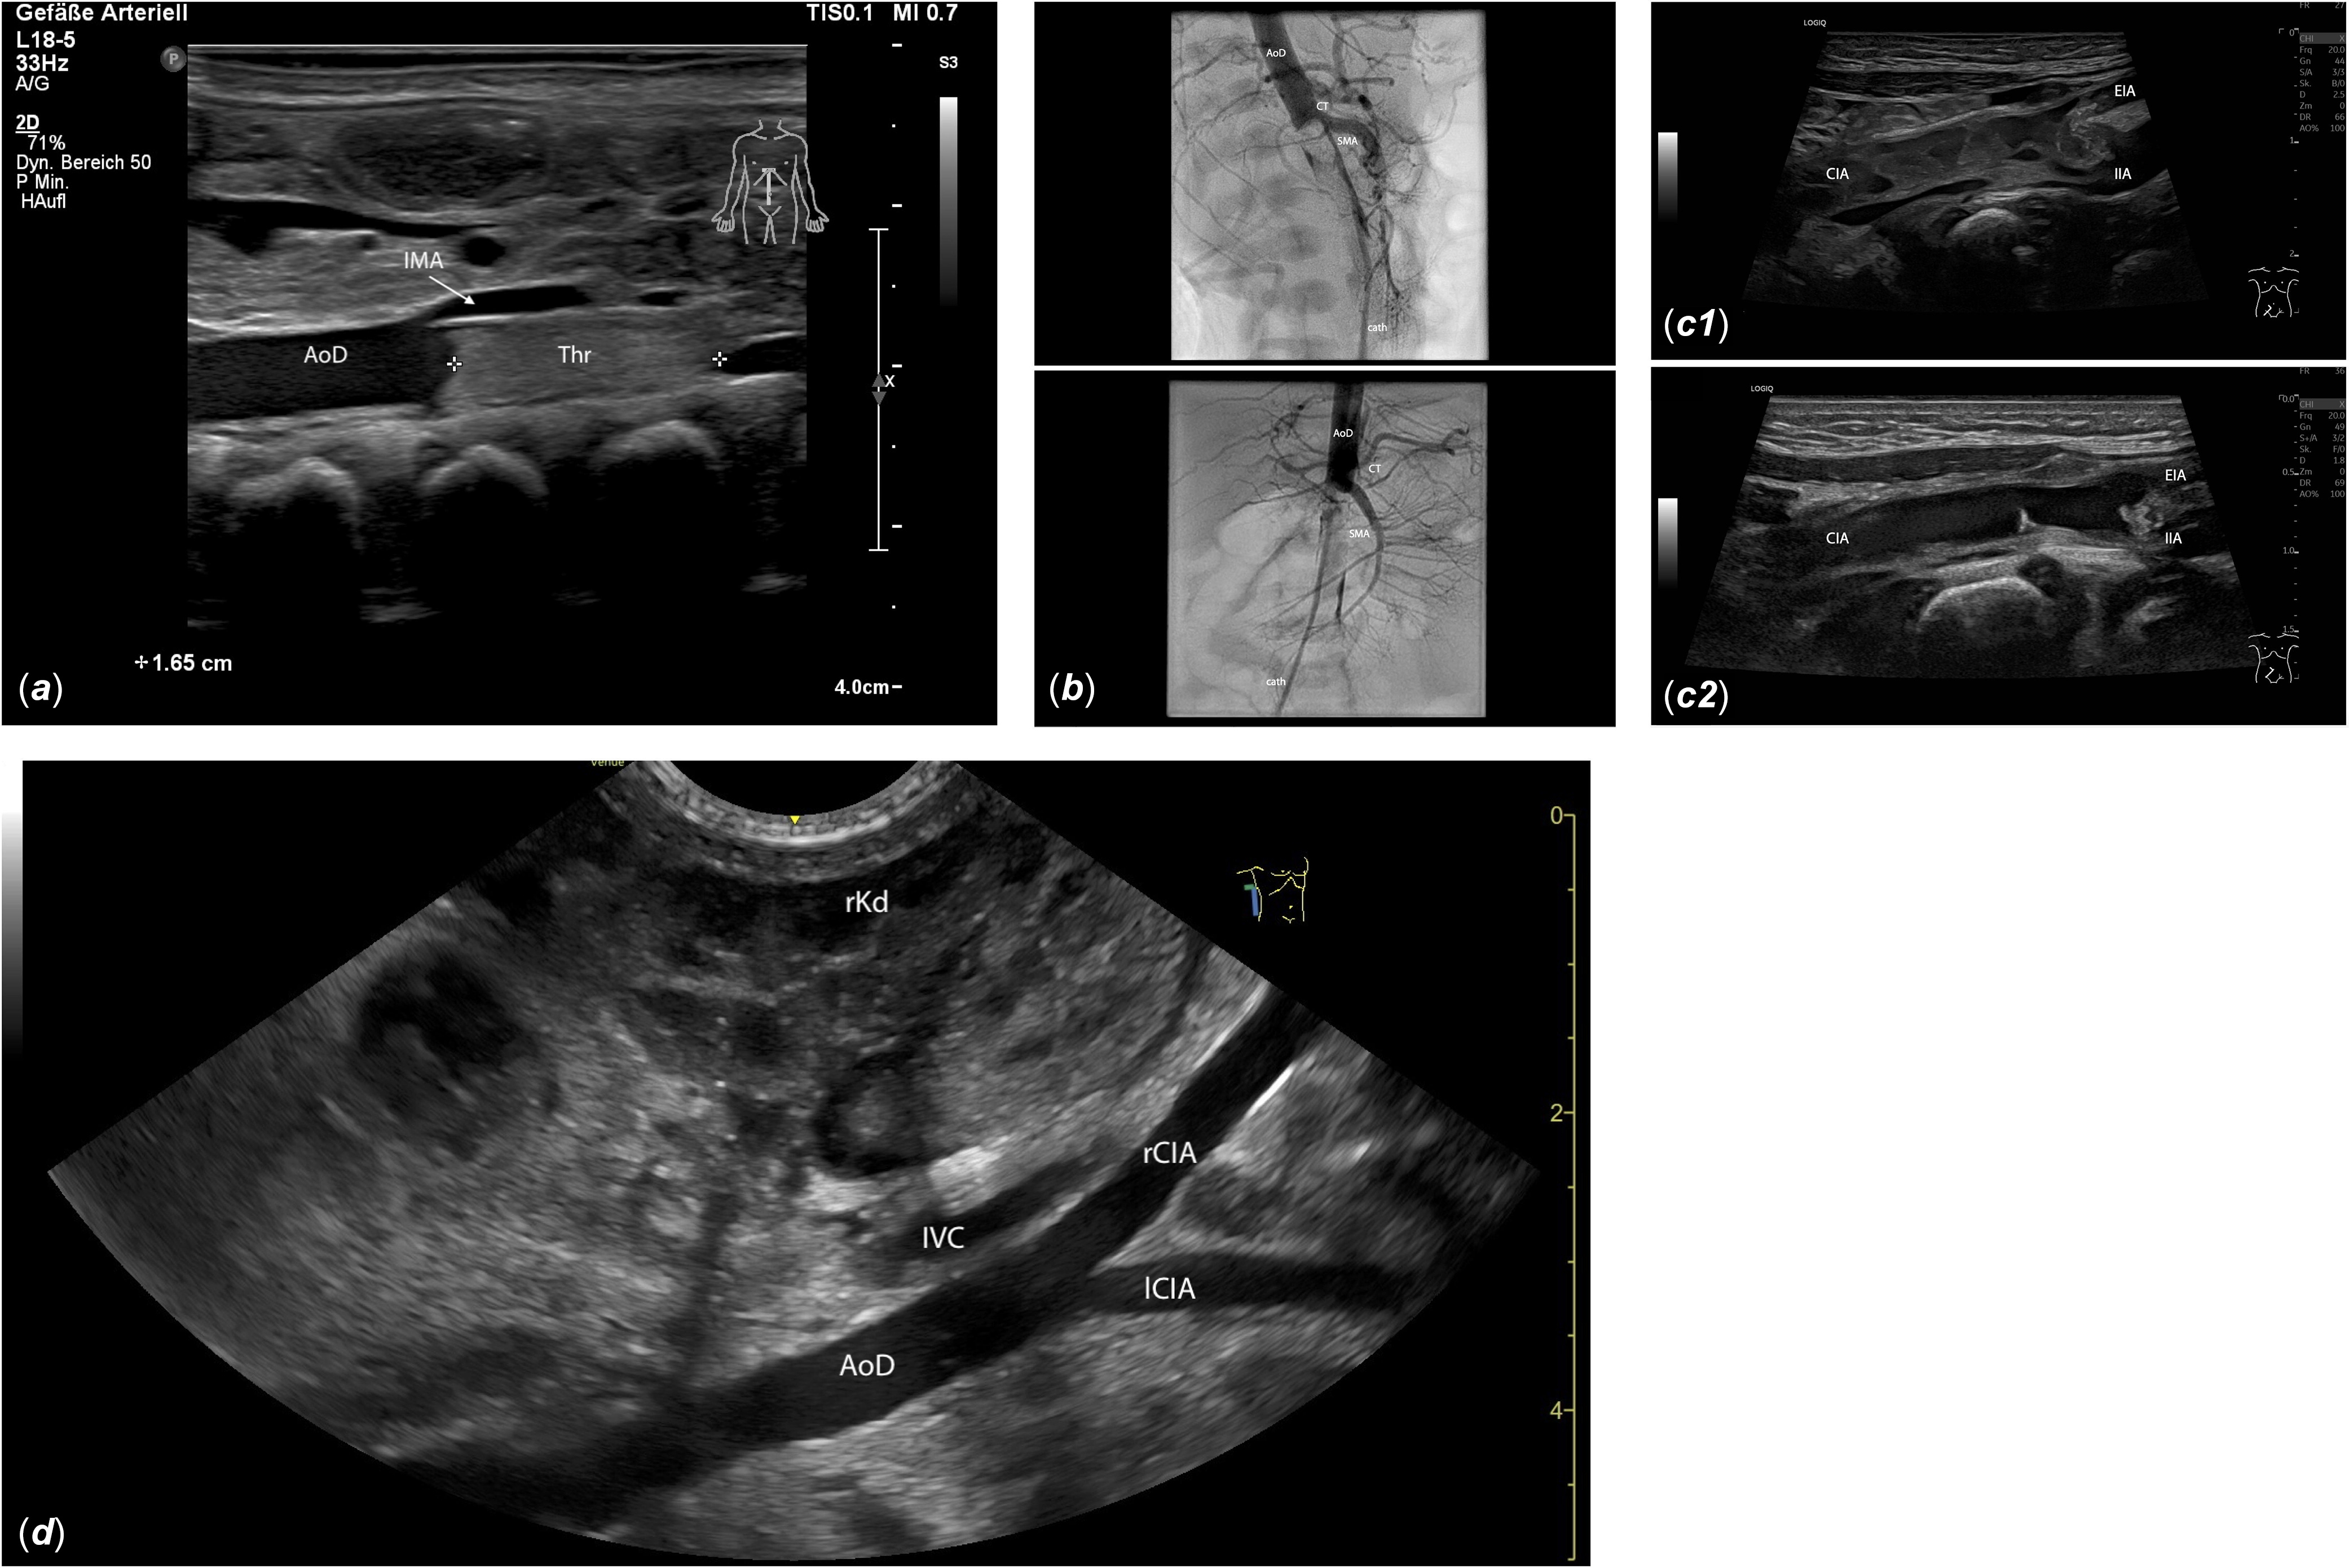

Figure 1. (a) Longitudinal midline view of the upper abdomen: A 1.65 cm hyperechogenic thrombus (Thr) is visible in the descending aorta (AoD), distal to the inferior mesenteric artery (IMA), extending into the aortic bifurcation. (b) The interventional angiography shows a contrast medium filling defect distal to the superior mesenteric artery (SMA), indicating a large thrombus obstructing blood flow to both renal arteries and the lower extremities. AoD: descending aorta; cath: catheter; CT: celiac trunk. For video see video supplement 2. (c) Oblique view of the right-sided inguinal region: C1, 10 days post interventional thrombectomy: inhomogeneous, dissolving thrombotic material extends from the common iliac artery (CIA) beyond the iliac bifurcation into the external iliac artery (EIA) and the internal iliac artery (IIA). C2, 17 days post interventional thrombectomy: The thrombus in the CIA is nearly dissolved, with only small hyperechogenic thrombus remnants visible on the vessel wall. The right EIA remains thrombosed, but the lumen of the proximal right IIA is largely restored. (d) View from the right flank: Imaging of the descending aorta (AoD) and the right and left common iliac arteries (rCIA, lCIA) is generally clearer from the flank than from the midline due to reduced intestinal gas interference. IVC: inferior vena cava; rKd: right kidney.

A eutrophic male neonate (39 2/7 weeks of gestation, birth weight: 3270g) was born in an external hospital with a paediatric cardiology department via vacuum extraction, exhibited delayed adaptation and required continuous positive airway pressure support. The lower half of the body remained pale, cold, and mottled, despite good perfusion in the upper body, in addition perinatal acidosis was present (umbilical artery pH: 7.01, BE: −10.4 mmol/L, APGAR 2/7/8). Echocardiography revealed normal left ventricular function and an unremarkable aortic arch, while abdominal ultrasound detected a thrombus at the aortic bifurcation with significantly reduced flow velocities in the iliac vessels (Figure 1A). Following consultation with Hannover Medical School, therapeutic heparinisation (400 IU/kg/day) was initiated, and the patient was promptly transferred to Hannover with continuous positive airway pressure support. Laboratory tests on admission showed no evidence of kidney dysfunction (creatinine: 76 µmol/L) but indicated impaired liver function with an ALT of 75 IU/L, an aspartate aminotransferase (AST) of 150 IU/L, and a Quick of 39%. The D-dimer was markedly elevated at 22.79 mg/L. The newborn was intubated on the day of transfer due to impending respiratory exhaustion. Given the patient’s overall condition, systemic thrombolysis with rt-PA was chosen as the primary therapy. In accordance with the German guidelines for thrombosis in children at that time, the child received rt-PA via continuous infusion for six days (starting at 1 mg/kg/day, with a maximum of 2 mg/kg/day), Reference Nowak18 followed by full heparinisation (400 IU/kg) for 24 hours before transitioning to subcutaneous enoxaparin for six months (1.5 mg/kg twice daily, targeting anti-Xa levels: 0.6–0.8 IU/mL). During thrombolysis, ultrasound examinations were performed three times a day to detect any signs of intracranial, adrenal, or abdominal bleeding, with no complications observed. Laboratory monitoring showed a decline in D-dimer from 22.79 mg/L on admission to 3.94 mg/L by discharge, and an improvement in Quick from 39 to 71%. The aortic thrombus regressed under systemic thrombolysis and was no longer detectable by the time of discharge on the eighth day of admission. Clinically, the sonographic findings correlated with strongly palpable inguinal pulses and normal skin perfusion in the lower extremities. The boy’s subsequent psychomotor development was entirely normal. Thrombophilia screening, performed partly during the acute phase and completed three months after initial hospitalisation, revealed no evidence of a prothrombotic disorder, including antithrombin deficiency, protein C/S deficiency, antiphospholipid syndrome, prothrombin G20210A mutation, factor V Leiden mutation, and dysfibrinogenemia.

With multi-organ failure imminent and a suspected diagnosis of an aortic thrombus, an emergency cardiac catheterisation via the right femoral artery was performed. Angiography confirmed a thrombus completely obstructing the descending aorta below the celiac trunk, extending partially into the superior mesenteric artery. The distal abdominal aorta, including both renal arteries and the lower extremities, was not perfused (Figure 1B). Additionally to local rt-PA thrombolysis (1 mg/kg), a technically complex mechanical thrombectomy was performed using off-label vascular plug devices (Amplatzer Vascular Plug II 6 + 8 mm, St Jude Medical, St Paul, Minnesota, USA) as an “alternative thrombectomy tool” and balloon angioplasty to address residual thrombus material in the iliac arteries bilaterally, resulting in successful reperfusion of the entire descending aorta and its branches, including both iliac arteries (video supplement 2–3). As small thrombus fragments persisted in the iliac vessels, systemic thrombolysis (rt-PA, 2 mg/kg) was administered, followed by therapeutic heparinisation (maximum 650 IU/kg/day) continued for six days, targeting an individualised partial thromboplastin time (PTT) range around 50–70 seconds. Subsequently, tinzaparin was administered at 275 IU/kg once daily, targeting anti-Xa levels between 0.6 and 1.0 units. Following the intervention, the patient’s ventricular function improved rapidly, allowing extubation after 4 days. Catecholamine therapy (epinephrine, norepinephrine) was discontinued after 5 days. Renal function recovered quickly, with creatinine levels returning to normal by the time of discharge. Follow-up sonography, performed every two days, revealed a marked reduction in the thrombus size in the iliac vessels, with successful reperfusion of the abdominal aorta, the superior mesenteric artery and the left internal and external iliac arteries (video supplement 4). The right internal iliac artery was also reperfused. The right external iliac artery remained thrombosed and obliterated, with good collateralisation compensating for the loss (Figure 1C). Aspirin was started shortly before discharge at a dose of 1–2 mg/kg once daily. Tinzaparin was discontinued after four months, and aspirin after eleven months.

Cases 1 and 3 presented with significant clinical deterioration characterised by nonspecific symptoms such as lethargy, feeding difficulties, weight loss, and decreased urine output. Such signs can occur in a variety of neonatal conditions (e.g., infection, metabolic disorders, congenital heart defects), necessitating thorough clinical evaluation, including vital signs, blood pressure measurement in all four limbs, and pulse oximetry of upper and lower extremities. Importantly, careful palpation of femoral pulses is essential, as abdominal aortic thrombosis typically manifests with diminished or absent femoral pulses. The differential diagnosis for absent femoral pulses in a critically ill neonate includes coarctation or interrupted aortic arch. Reference Wieland, Jack and Seidemann14 Clinical differentiation of aortic thrombosis from coarctation can be challenging; however, symptoms like pallor, pain, and poikilothermia are more indicative of thrombosis. Rapid echocardiography by an experienced paediatric cardiologist is crucial to assess cardiac function, aortic arch anatomy, and exclude structural defects. When coarctation or interrupted arch is excluded, abdominal Doppler sonography should be performed to confirm or exclude thrombosis. Sonography is the most valuable diagnostic tool for detecting aortic thrombosis because it is readily available and non-invasive. Approximately 80% of aortic thromboses are diagnosed by sonography. Reference Nagel, Tuckuviene and Paes7 Typical sonographic findings include visualisation of intraluminal thrombus, echogenic in organised thrombi and hypoechoic in acute stages, as well as abnormal Doppler flow patterns such as absent or turbulent flow. Reference Tsung, Nickels and De Portu21 Visualisation of the abdominal aorta can be challenging due to intestinal gas, but imaging from the right or left flank, near the kidneys, can help avoid gas interference (Figure 1D). Flow in the celiac trunk, superior mesenteric artery, both renal arteries, and the iliac vessels should be documented.